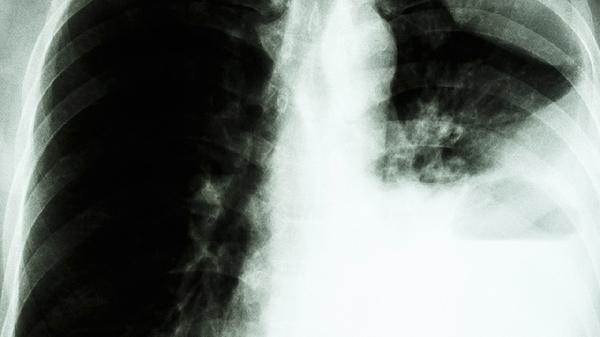

肺結節(jié)的治療方式主要有定期隨訪觀察、藥物治療、手術切除、射頻消融治療、冷凍消融治療等。肺結節(jié)的治療需根據(jù)結節(jié)大小、形態(tài)特征、生長速度及患者個體情況綜合評估。

高度懷疑惡性或直徑超過10毫米的肺結節(jié),可能需胸腔鏡下肺楔形切除術或肺段切除術。術中快速病理檢查可明確結節(jié)性質,若確診惡性需擴大切除范圍。術后需進行呼吸功能鍛煉,預防肺不張等并發(fā)癥。手術適應癥需嚴格評估患者心肺功能及手術耐受性。